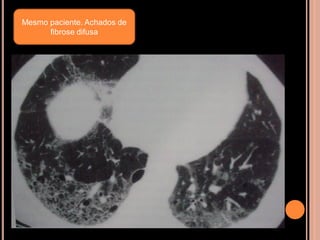

Mesmo paciente. Achados de

fibrose difusa

Avaliação para cirurgiade redução do volume pulmonar

Mesmo paciente. Achadosde fibrose difusa